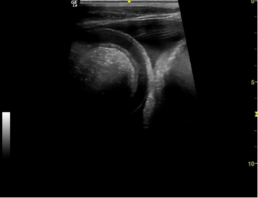

Rand des Magens (links im Bild), unauffällige Milz (rechts im Bild)